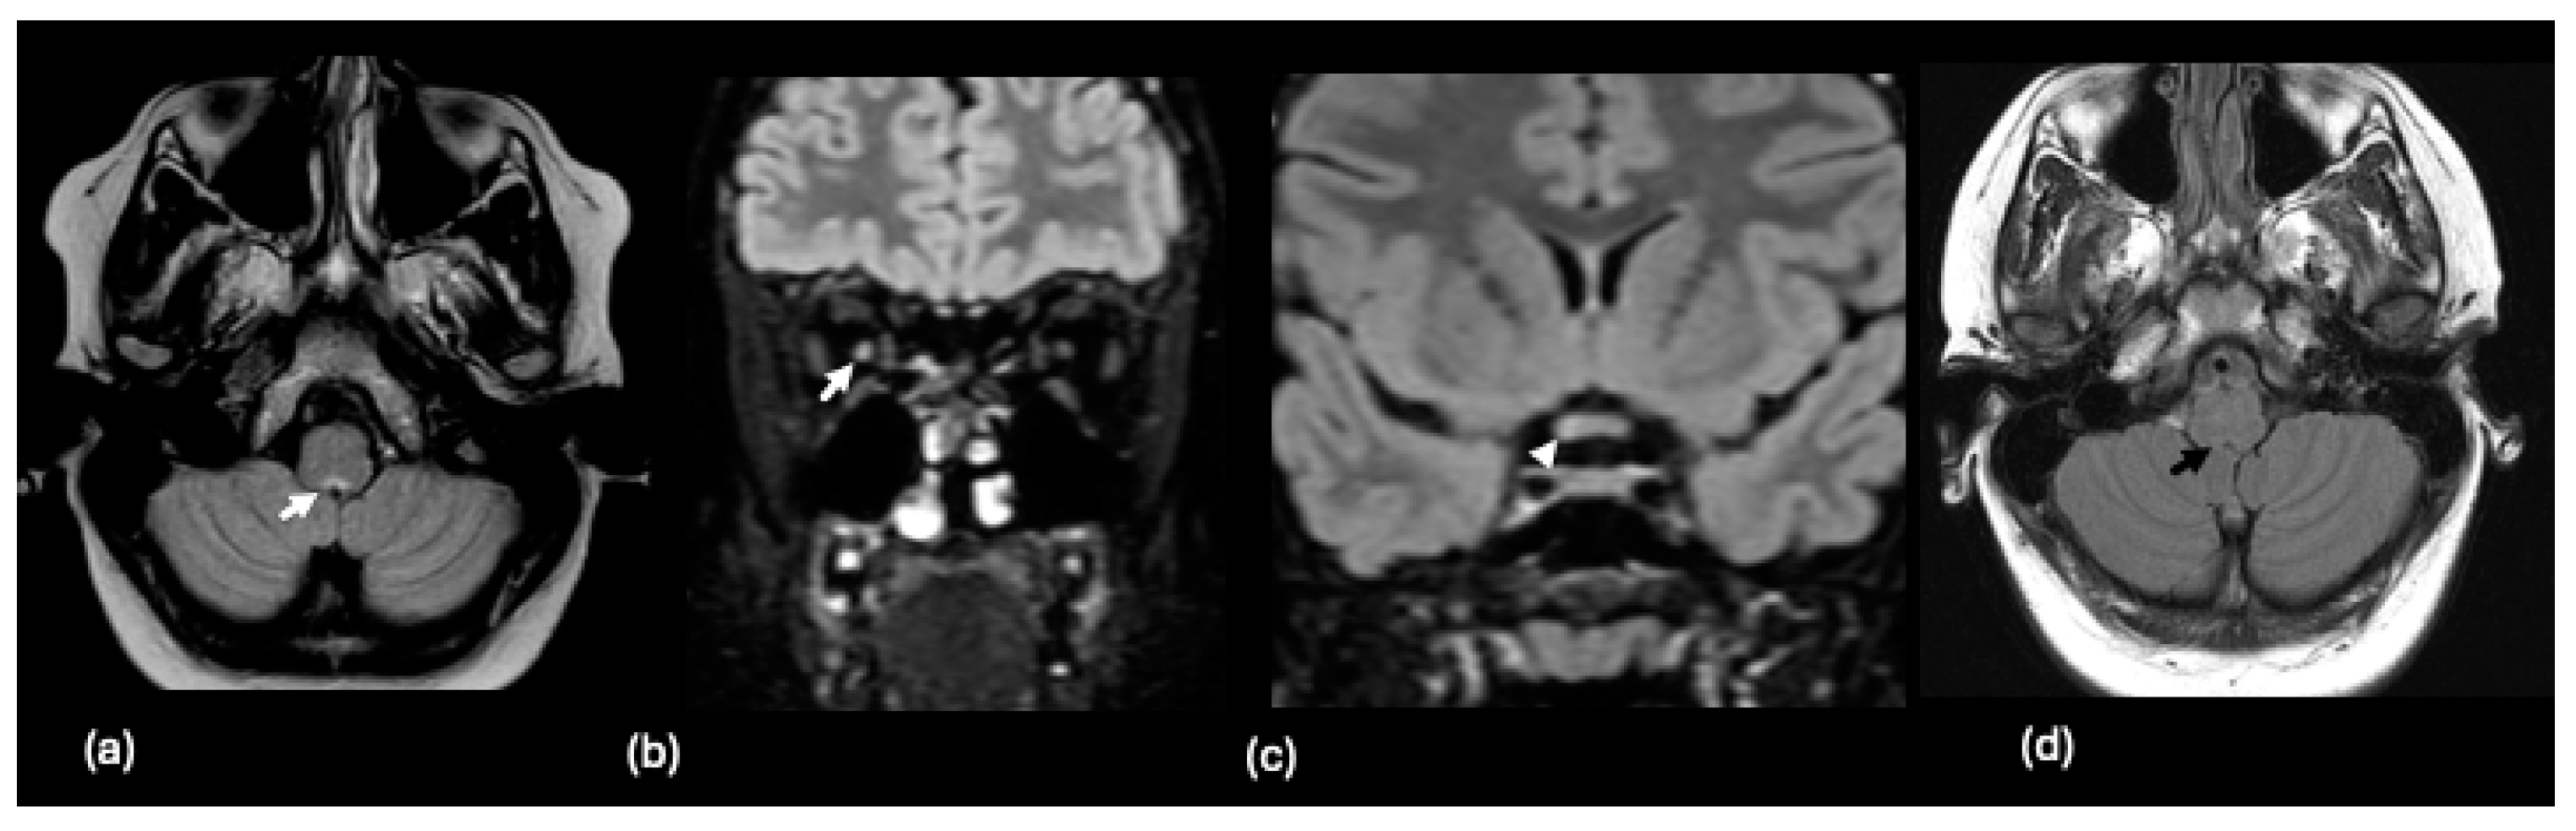

| MOGAD | MOGAD | Corpus callosum, orbital frontal gyrus, thalamus, basal ganglia, cerebellar peduncles, brainstem; Spinal cord -longitudinally extensive transverse myelitis | Less common; 25% spinal | Large, confluent, leukodystrophy-like lesions; curvilinear corpus callosal lesions, lesions with borders not well-defined in young children |

| MOGAD-associated ADEM | Bilateral supratentorial, subcortical white matter, deep white matter, deep gray matter (thalamus) | |||

| MOGAD-associated NMOSD | Periventricular lesions, periaqueductal grey matter, dorsal brainstem | |||

| MOGAD-associated ON | Swelling of the anterior optic nerve, optic nerve sheath; bilateral involvement | |||

| MOGAD-associated AE | Confluent subcortical white matter, cortical and deep grey matter lesions | |||